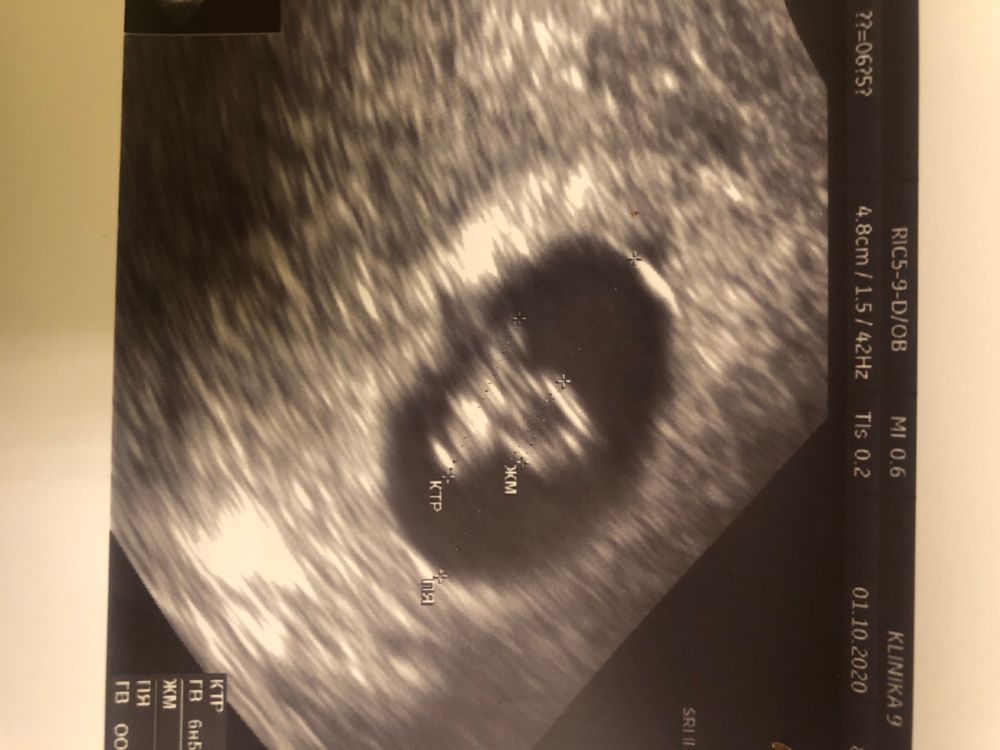

Узи 6 недель 5 дней

Увидели нашу крошку) 7 мм, сердечко 124 удара в минуту. Все хорошо, развитие по сроку. Через пару недель на учёт вставать)